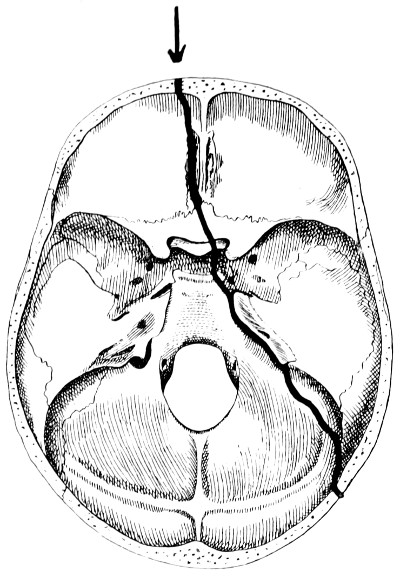

| 32-37. The lines pursued by basic fractures | 83-8 |

| 38 A and B. To illustrate the probable source of profuse hæmorrhage from the ear | 97 |